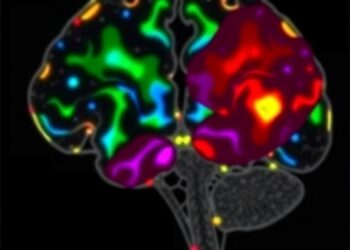

In this study, spearheaded by Habich, Baumann, Schwarz, and their colleagues, researchers employed imaging transcriptomics, a cutting-edge methodological framework that combines neuroimaging data with transcriptome maps. This approach helps pinpoint the locational alignment of gene expression patterns with observed cortical thinning and subcortical atrophy in DLB patients. By cross-referencing large-scale transcriptomic databases with structural MRI scans, the team delineated gene-brain atrophy correlations that shed light on region-specific susceptibilities.

One of the pivotal discoveries demonstrated that distinct clusters of genes involved in synaptic function, lysosomal activity, and proteostasis align spatially with regions exhibiting significant atrophic changes. Notably, genes implicated in alpha-synuclein metabolism—a hallmark protein aggregate in DLB—showed enriched expression within atrophy-prone areas. This reinforces the pathological relevance of alpha-synuclein’s misprocessing and accumulation in shaping neurodegenerative trajectories.

A highlight of the research involves the identification of regionally selective vulnerability that could explain the clinical heterogeneity observed among DLB patients. By mapping transcriptomic landscapes onto atrophic patterns, investigators uncovered genetic profiles unique to vulnerable subcortical nuclei and cortical regions governing cognition and motor control. This granular insight paves the way for tailored interventions targeting region-specific molecular pathways.

Technological breakthroughs in multi-modal data integration underpinned the success of the study. High-resolution magnetic resonance imaging furnished precise quantifications of gray matter volume reductions, while publicly accessible brain transcriptome atlases enabled comprehensive gene expression mapping. Sophisticated bioinformatics pipelines coupled these datasets, allowing robust statistical inference while mitigating confounding factors such as age-related changes and comorbidities.